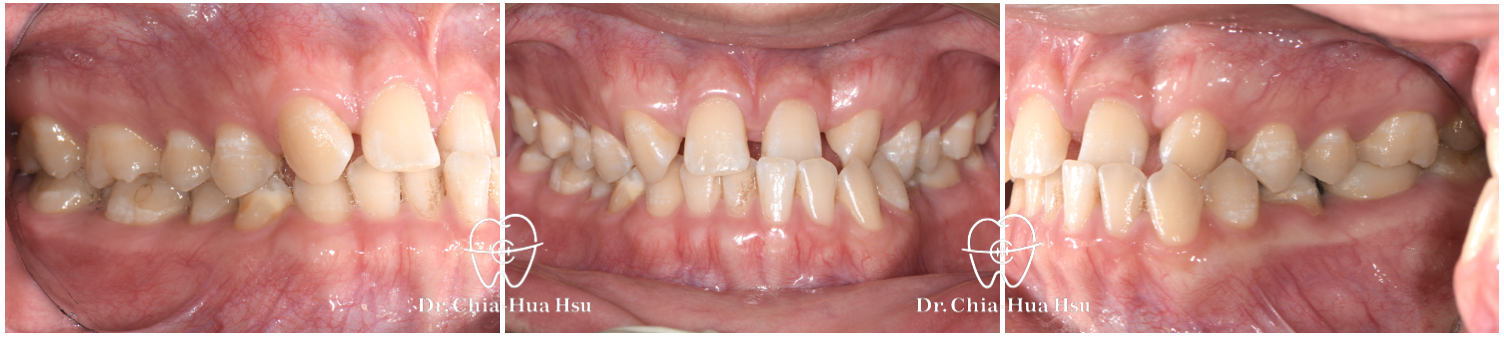

治療前

• 病患主訴:在意門牙牙縫和齒列不正。

• 問題分析:患者除了門牙牙縫、齒列不正問題,有先天性缺失上顎雙側側門牙兩顆以及左下第二小臼齒,並且左下方有滯留的乳臼齒,治療難度高。